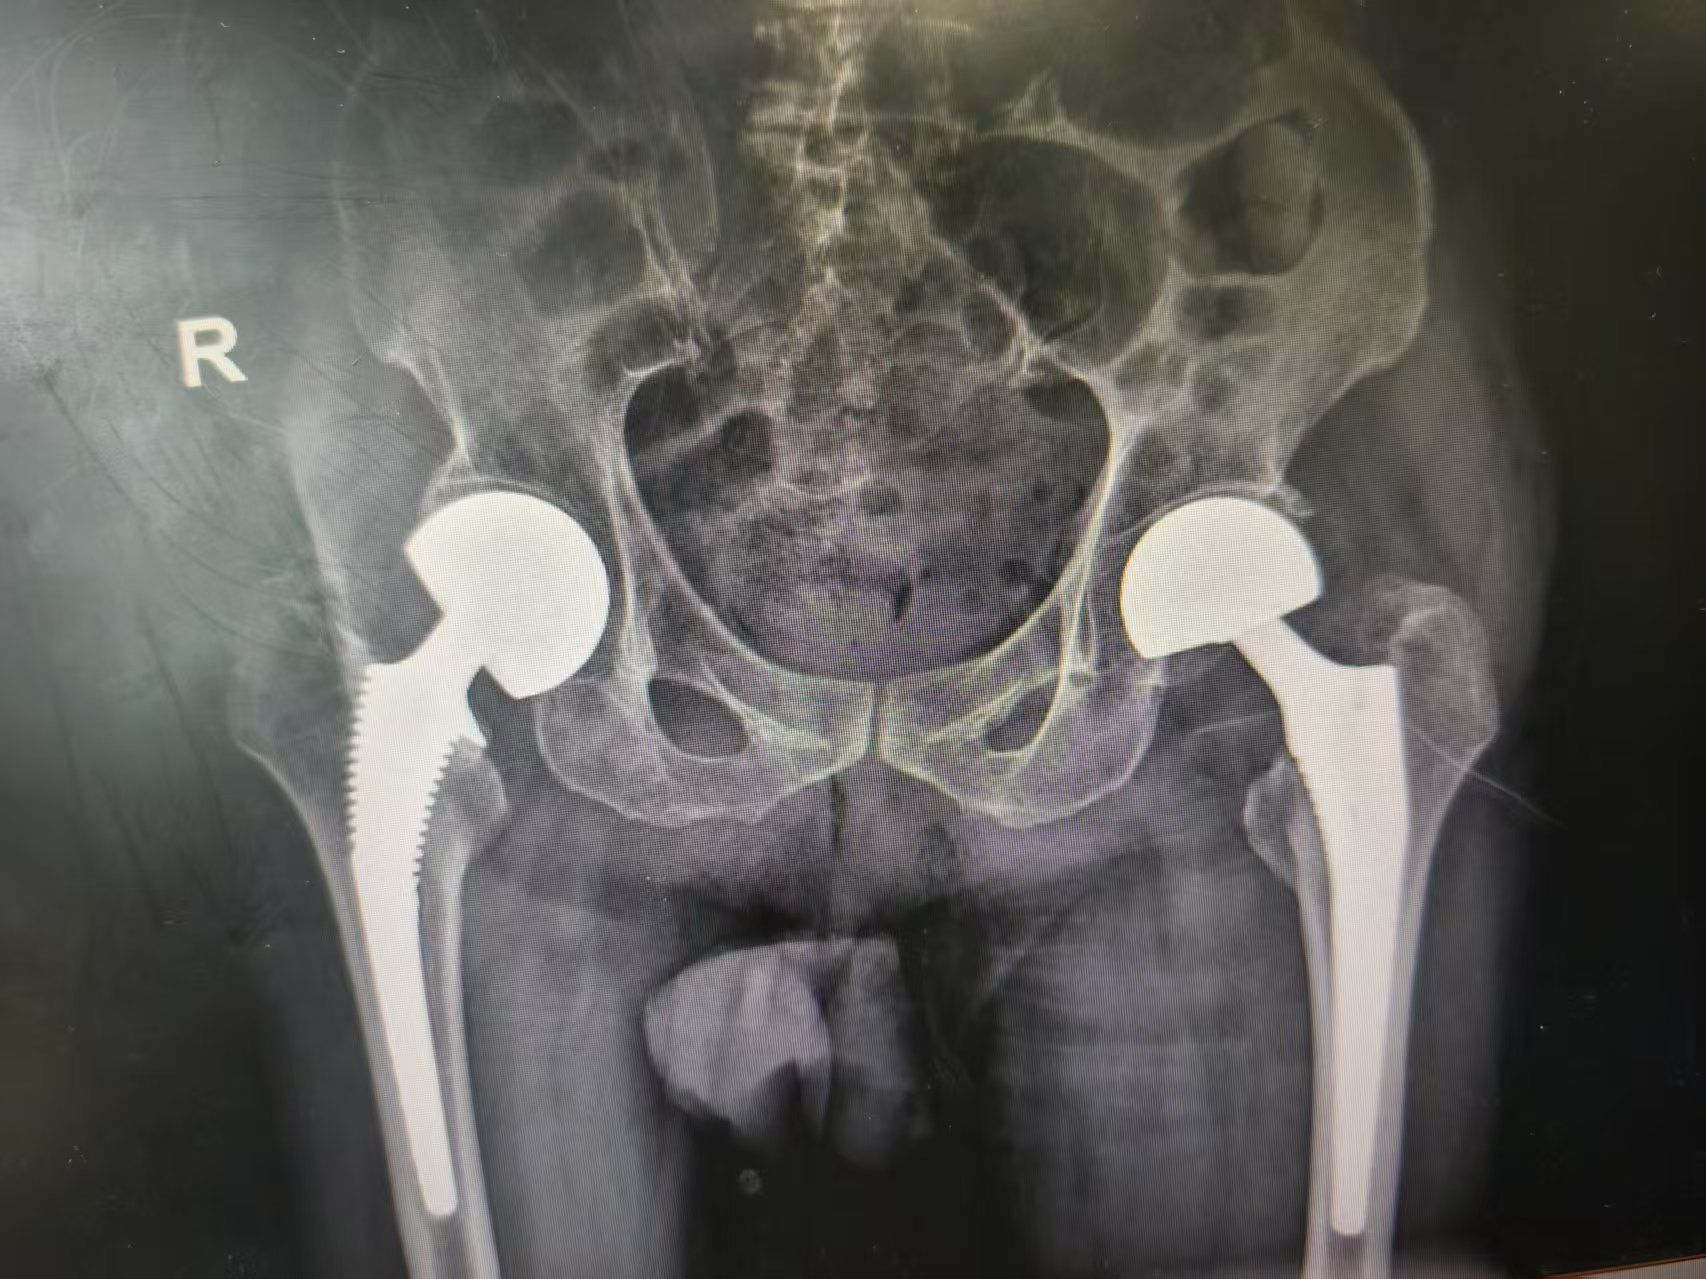

骨科主任醫師魯厚根與副主任醫師陸圣君形成精密配合,在血管神經的間隙中穿行,拔除股骨頭、清理髖臼窩內殘留的圓韌帶、植入生物型假體柄等操作一氣呵成。“髖關節松緊合適,植入假體包容性好。”顯示屏上銀白色的假體與殘存骨質完美嵌合,人工股骨頭置換手術僅用時30分鐘。

人工股骨頭置換手術術后影像。